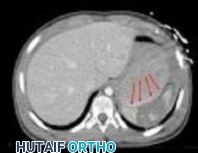

year-old boy who was found unresponsive after a diving accident. He had to be extricated from the bottom of a swimming pool by friends and was intubated at the scene by paramedics. In the emergency department, he was found to have weak triceps and grip strength bilaterally. Lower extremity strength was trace (grade 1 of 5). Sensation was diminished below the T2 dermatome. He had an absent bulbocavernosus reflex. Immediate open posterior reduction and stabilization were performed. Postoperative MRI revealed no iatrogenic disk herniation. Postoperative neurologic function revealed grade 4 strength in the triceps, wrist flexors, and bilateral grip. His lower extremity strength was grade 3. The sensory examination showed only slight diminution in the legs bilaterally. His bulbocavernosus reflex returned on postoperative day 2. On postoperative day 3, he required reintubation and was noted to require high positive end-expiratory pressures and a high ventilatory rate to keep him oxygenated. On postoperative day 4, his temperature was 38.7° C, blood pressure was 90/48, and pulse was 110 beats per minute. The urinary output measured 32 ml per hour. The white blood cell count was 14.8 with a left shift. A chest CT was ordered, and the results are shown in Figure 3. What best describes his condition?

4. Septic shock Discussion: D

Aspiration pneumonia developed, as seen on CT, and presumably occurred during his near drowning accident. His laboratory values and hemodynamic status are characteristic for septic shock. His original neurologic injury is an incomplete spinal cord injury, but after reduction and stabilization, he showed neurologic improvement, so this injury should not have contributed to his circulatory problems. The treatment for septic shock is broad spectrum antibiotics (species specific if the pathogen is identified) and pressors.